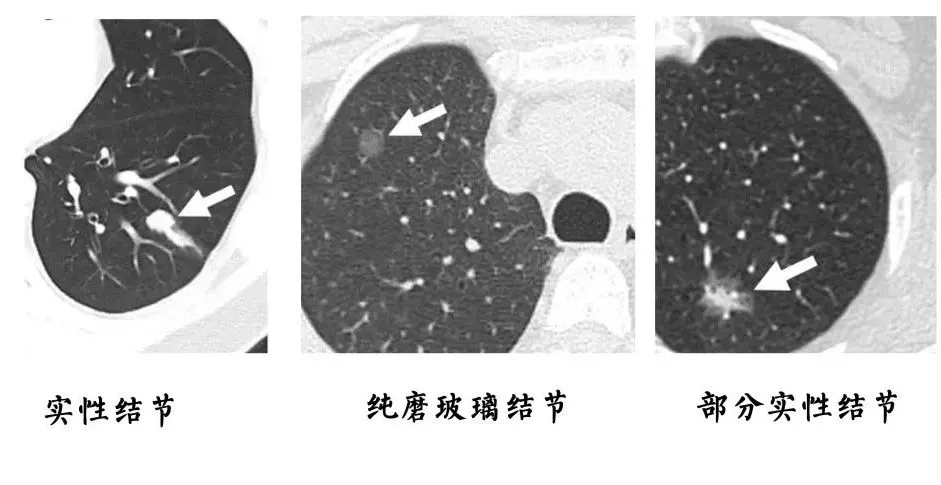

结节一般是指在CT、彩超、磁共振等检查中发现的直径小于3厘米的病灶。

医生会根据结节的形状、密度、血液供应等特点,来初步判断这些结节的性质。